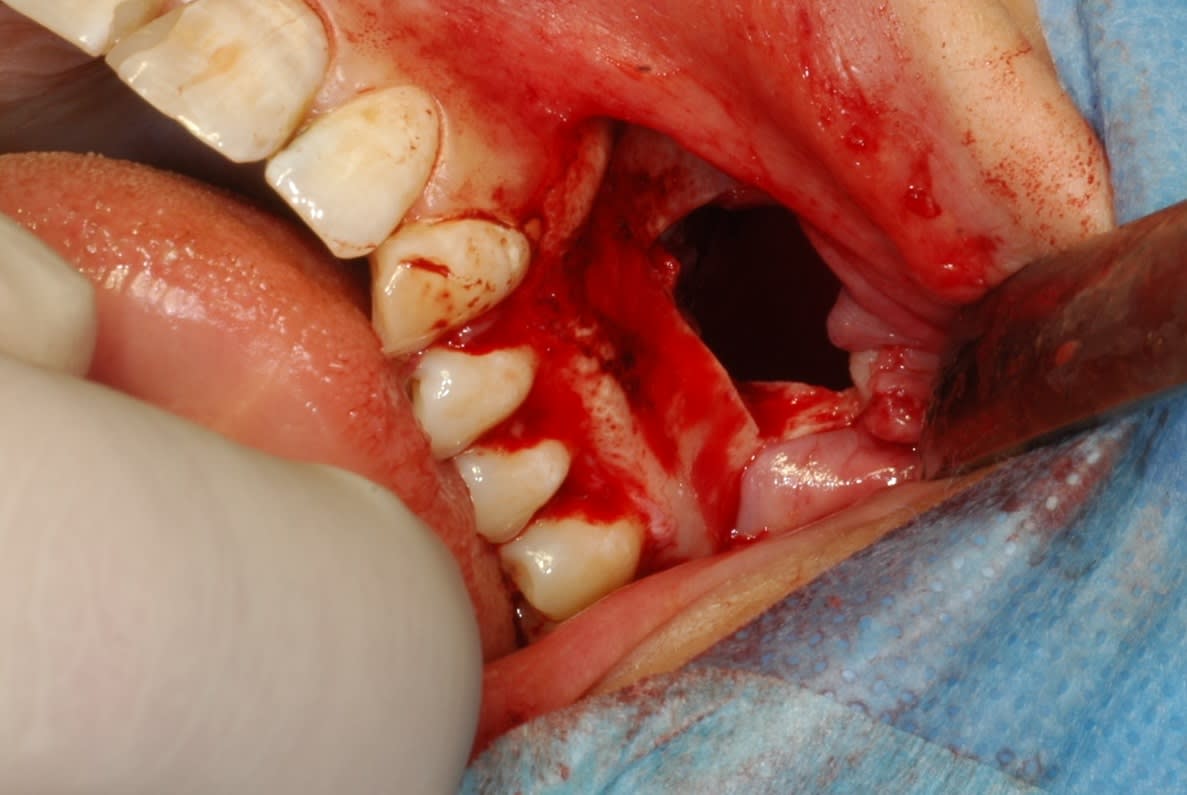

Y fait noir dans un sinus...

J attends vos critiques. Les photos sont pas top, mon assistante avait la bougeotte :0))

C est un kyste (je pense folliculaire) qui l a projetee au fil du temps dans le sinus.

Le kyste est venu tout seul. Par contre j ai du batailler pour la dent. Elle etait encloisonnee dans septas osseux contre paroi nasale a 90 degres a gauche en entrant :0))

Au scan j avais une idée.. sauf elle se cachait derrière double cloison. Ensuite fibre optique et contorsions pour l apercevoir.